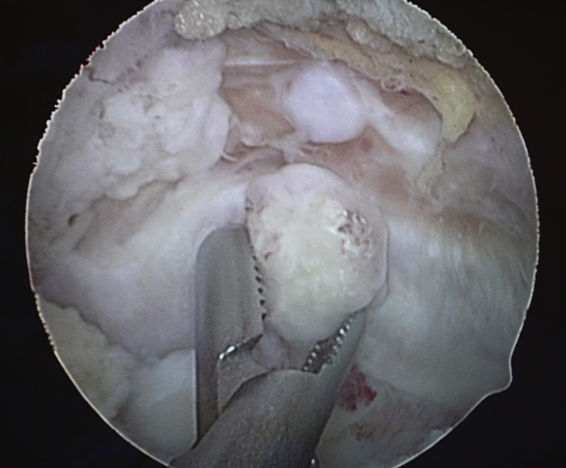

A simple surgery called elbow bone spur surgery should take care of that for you, without putting you out of action for. If nonsurgical treatments fail to relieve symptoms, arthroscopic surgery may be helpful to. They are usually painless unless they pinch nerves or tissues, in which case they have to be removed.

Although formal physical therapy after surgery is not usually needed, your doctor will recommend specific exercises to improve your range of motion. Although formal physical therapy after surgery is not usually needed, your doctor will recommend specific exercises to improve your range of motion. For those patients whose elbow spur cause persistent pain and also affect the mobility of the joint, the doctor will prescribe arthroscopic surgery. If nonsurgical treatments fail to relieve symptoms, arthroscopic surgery may be helpful to.